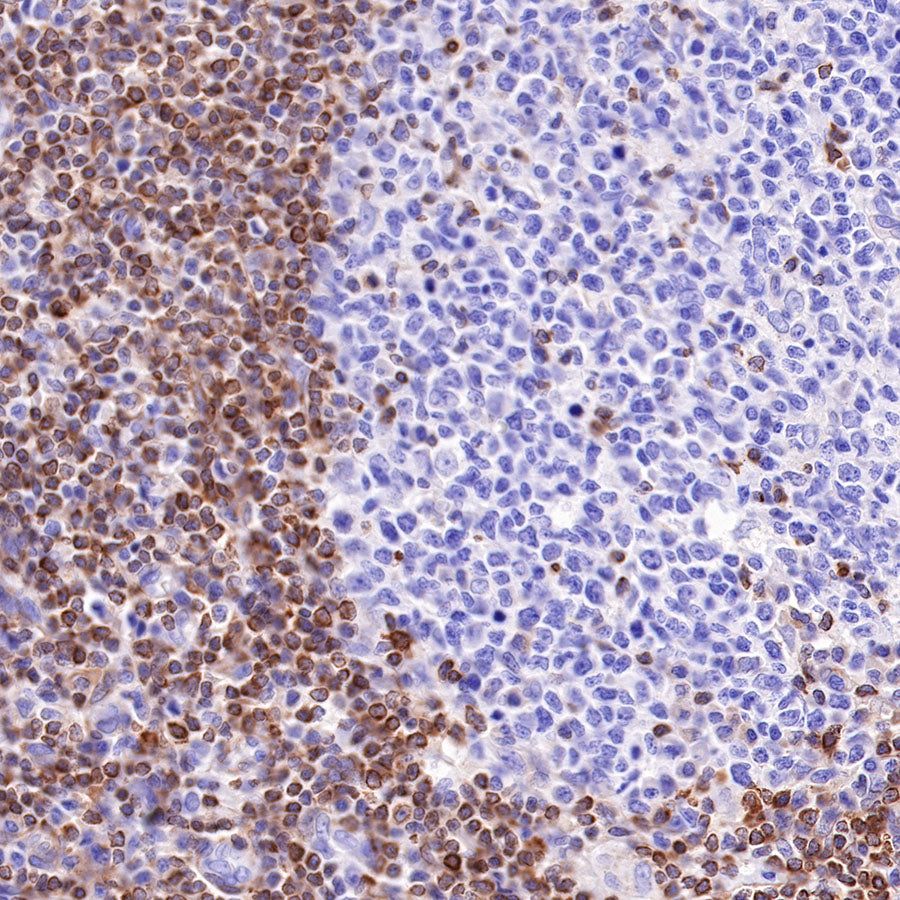

Picture

Picture

Immunohistochemistry